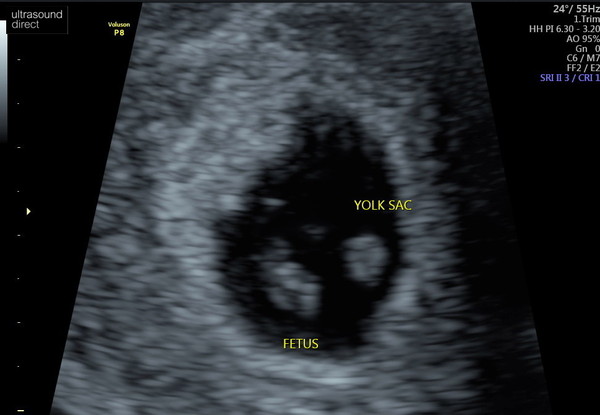

So I had my scan and it’s fine! Little baby with a heartbeat and she thinks I was just a week behind dates, so revised EDD of 12 April 2021.